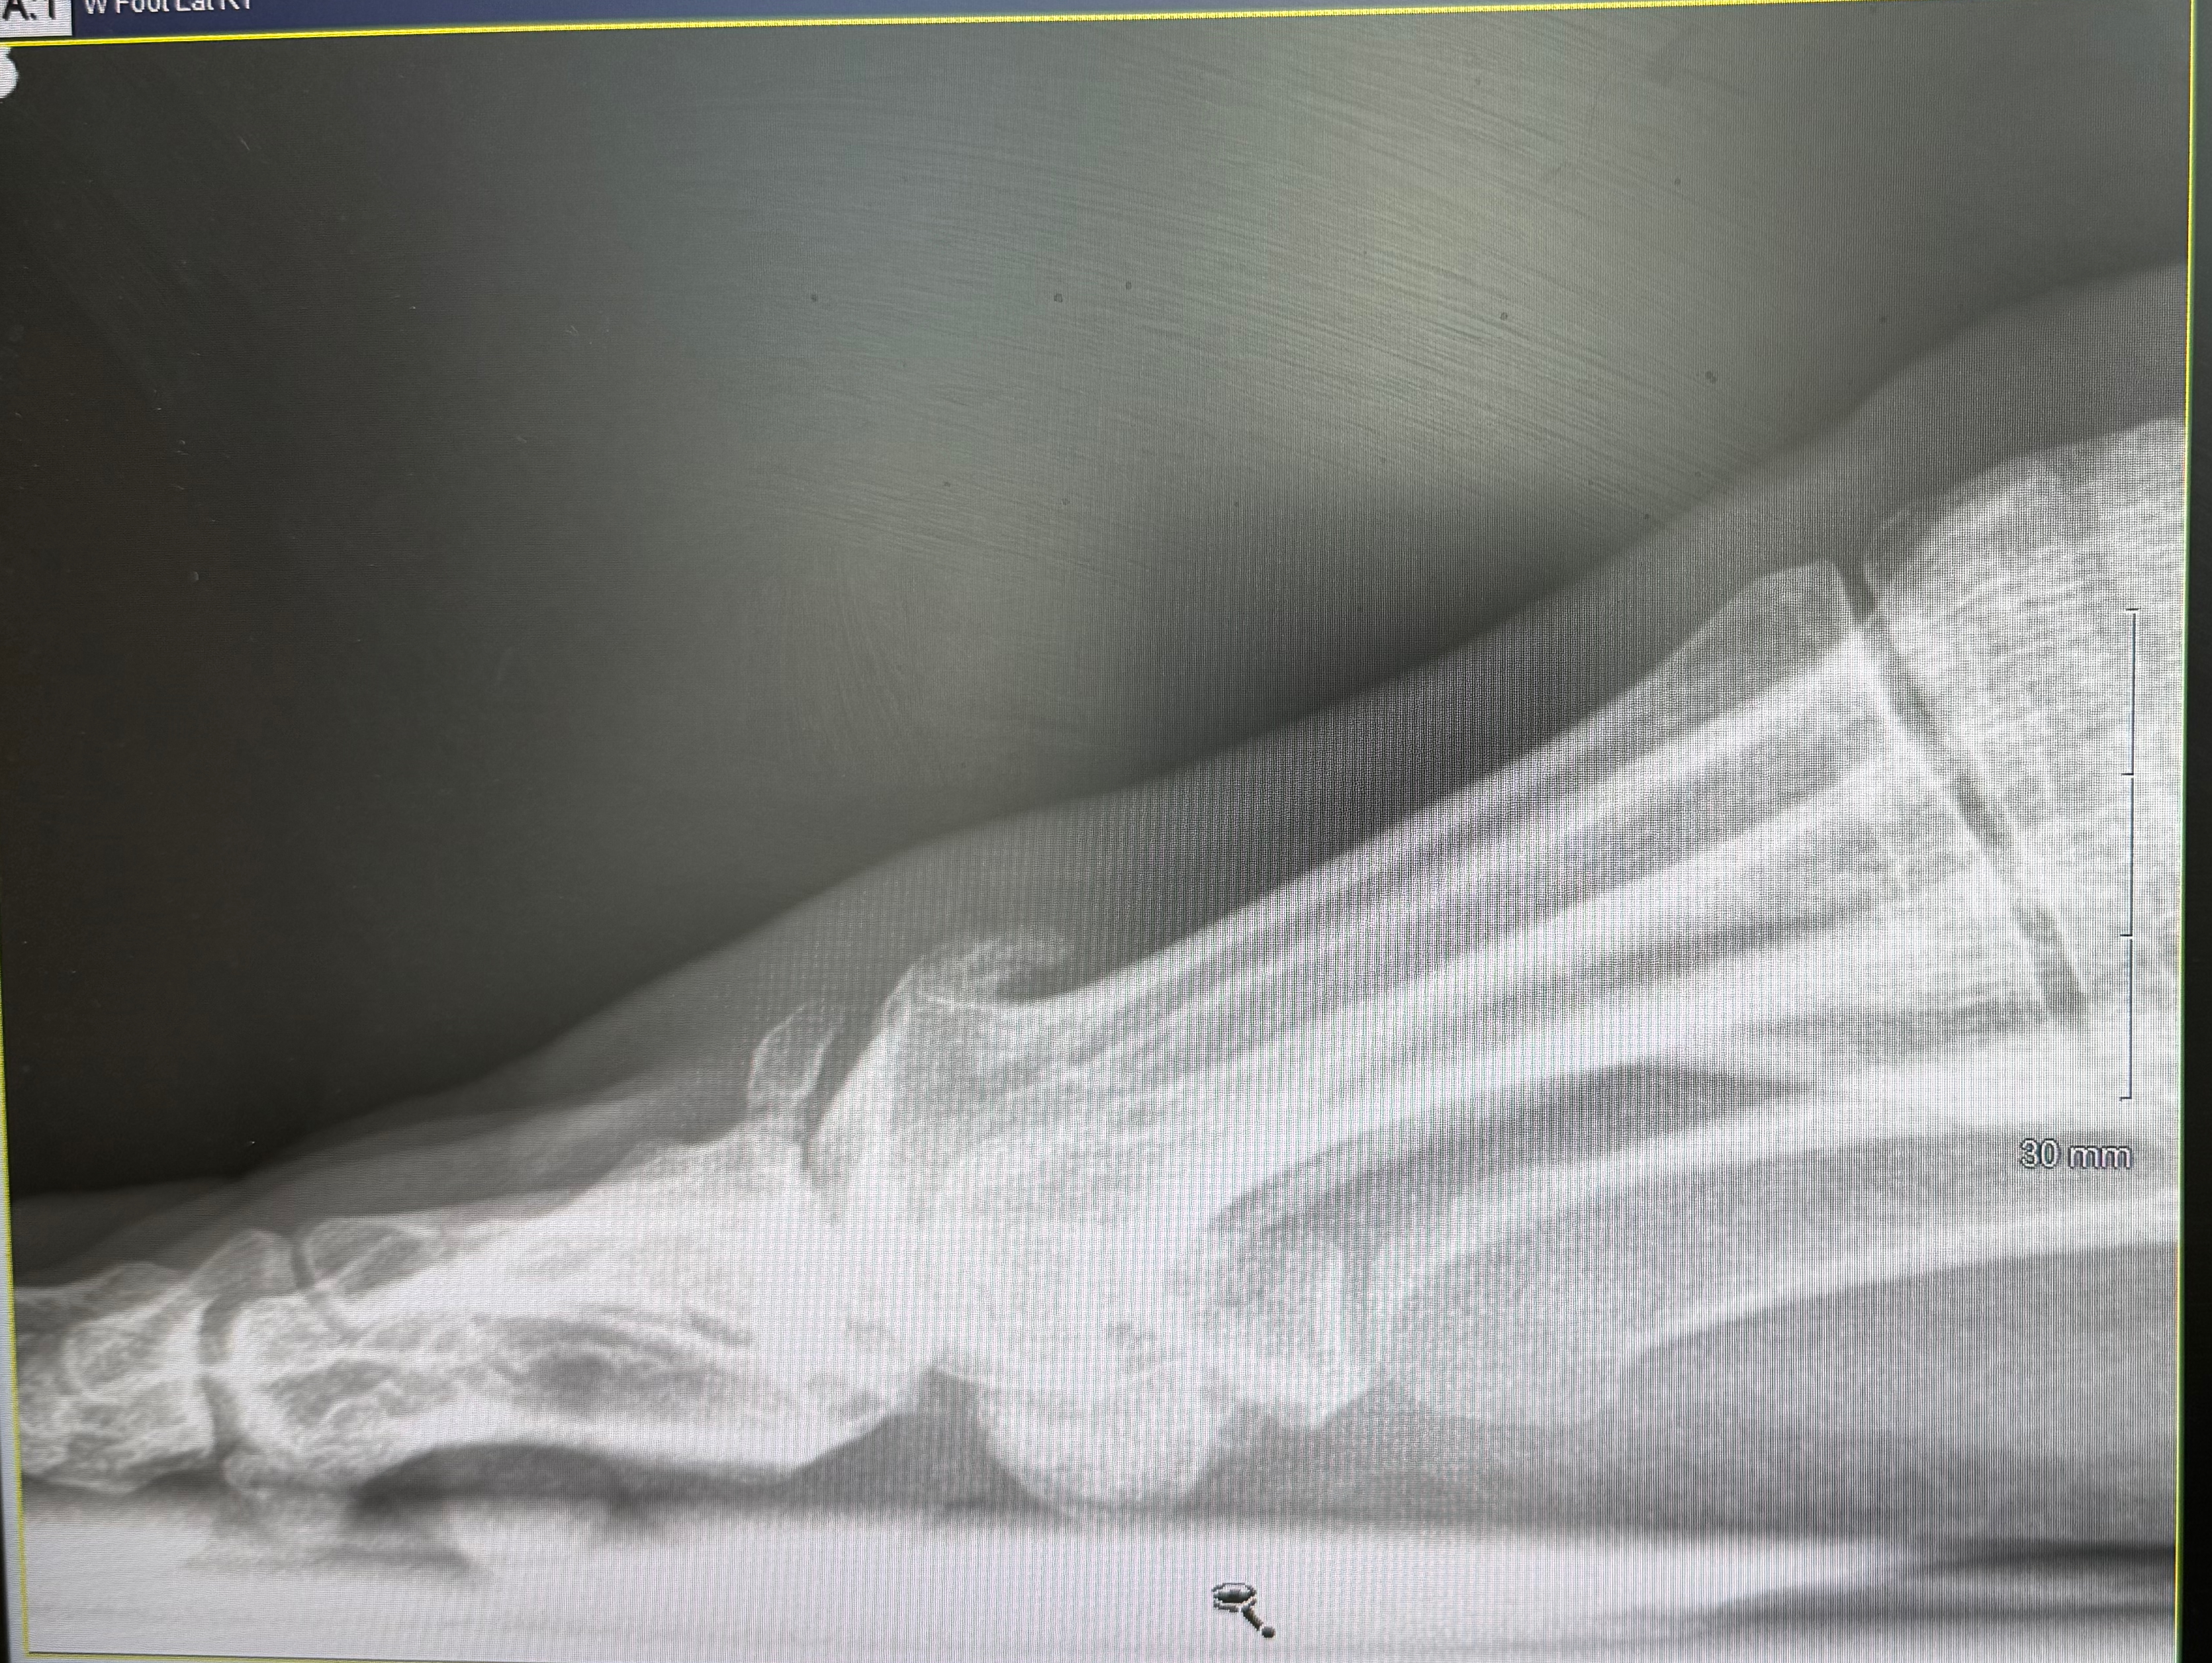

“See all those little bits in the X-ray? They’re tiny pieces of bone that are floating around, when they get into the joint you’ll notice that it hurts more than usual”

It did, I could hardly bend it at all, wearing sandals was totally out of the question, not only because my deformed foot was embarrassing to have on display.

“Look, it’s osteoarthritis, and it’s not going to get better on it’s own, and no steroid injection is going to help with all that rubble in there. I can fuse it if you want, that’ll help with the pain, but it’ll never bend again”.